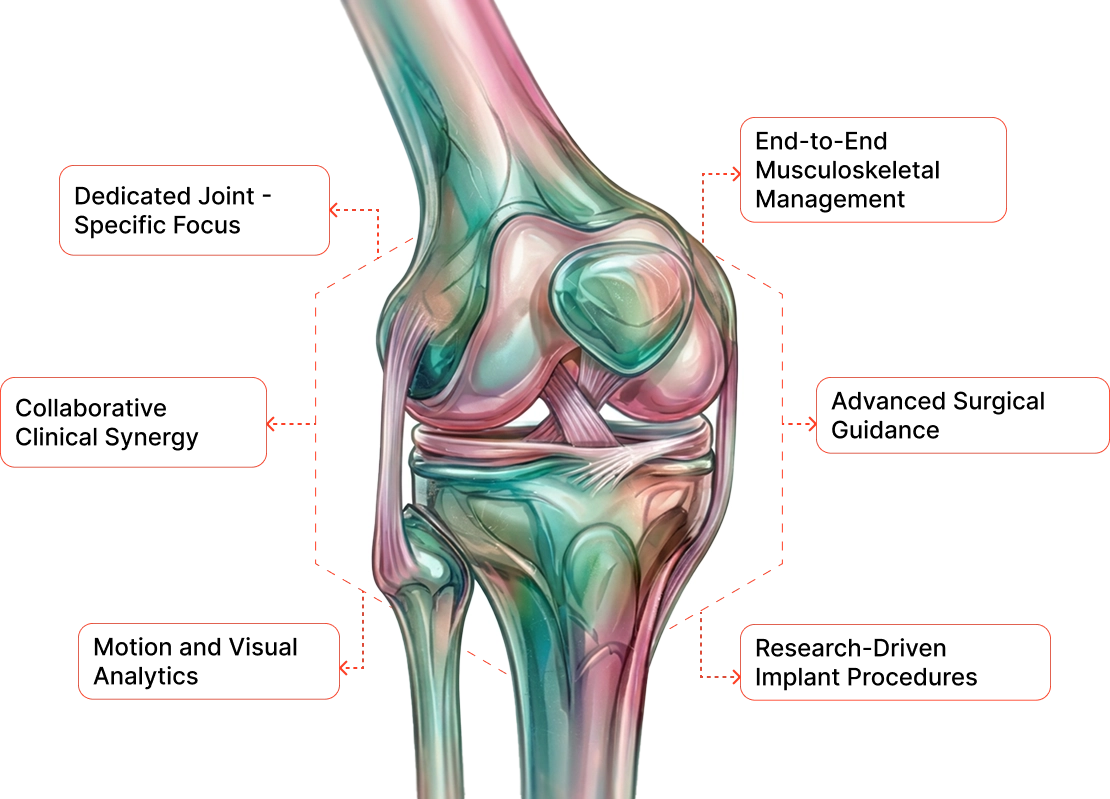

The Orthopaedics Institute at Anandam Hospitals stands as a centre of excellence, offering comprehensive care for musculoskeletal conditions across all age groups. Our multidisciplinary team, consisting of orthopaedic surgeons, pain management specialists, and physiotherapists, provides highly personalised treatment plans supported by state-of-the-art diagnostic and surgical technologies.

We specialise in joint replacements, sports injuries, trauma care, congenital conditions, and complex spine problems. Furthermore, our clinical experts are backed by specially trained staff who utilise cutting-edge techniques to ensure optimal patient outcomes. We remain dedicated to alleviating the burden of orthopaedic disorders through ongoing research, innovative treatments, and advanced joint implant designs.

The Orthopaedics department at Anandam Hospitals is a state-of-the-art centre dedicated to the end-to-end care of all musculoskeletal conditions across every age group, with a special focus on children, whose bone and joint requirements differ significantly from those of adults. Led by a distinguished team of world-renowned clinical experts, this multidisciplinary institute delivers comprehensive, personalised treatments designed to enhance our patients' overall quality of life. We specialise in joint replacements, the treatment of sports injuries, trauma management, congenital defects, and spinal problems.

We feature a dedicated, multidisciplinary team of joint-specific doctors and expert therapists.

Dedicated experts for each joint of the body are backed by specially trained nurses and occupational therapists who work together to ensure complete patient well-being, both pre- and post-surgery, guaranteeing optimal outcomes.

At Anandam Hospitals, experts from across various disciplines and specialties unite to comprehensively assess patients, offering the best possible treatment plan utilising the most advanced medical technology, techniques, and clinical protocols.

Latest Technology Utilisation

At Anandam Hospitals, we employ highly advanced orthopaedic technologies, including:

Utilized for the systematic analysis and precise assessment of human motion, allowing us to effectively plan treatments and significantly improve rehabilitation outcomes.

A state-of-the-art, computer-enabled tracking system that expertly guides surgeons in making highly precise cuts and corrections during complex surgical procedures.

High-resolution scientific imaging cameras that provide our surgeons with enhanced, highly detailed views of tissues, ensuring more accurate and effective treatments.